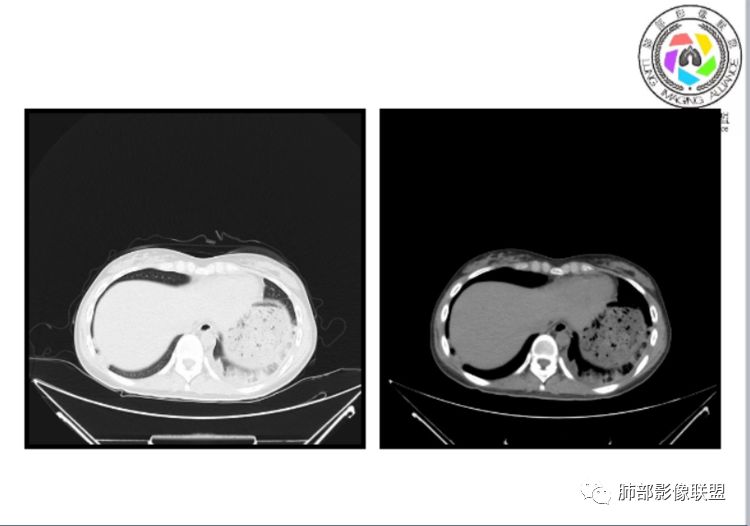

小微:右肺下叶斑片状密度增高影,抗炎治疗6天后复查,双肺下叶出现斑片状密度增高影,排除炎性病变,D2聚体特别高,考虑肺栓塞,肺梗死,建议增强扫描。王开金江津中心医院呼吸科:@岳微-辽宁PLA234医院放射科?支持,患者年轻女性,胸痛主诉,使用雌激素,高危人群,心率快,d二聚体升高,右下叶斑片加肺动脉明显增宽,抗感染无效,要考虑PTE,建议肺动脉ctpa。傅昌瑜:19岁,女性,右侧胸痛2天,发热以中度热为主,D—二聚体升高,肺动脉主干增宽,病灶位于胸膜下,抗感染后增多,近来有服用炔雌醇环丙孕酮片2周期史,诊断:肺栓塞,下一步完善肺CTPA检查。阿仙奴:青年女性,急性起病,胸痛入院,月经不调史,目前服用孕酮片。流感抗体阳性,d二聚体升高,无低氧血症。右肺下叶基底段胸膜下磨玻璃样改变,肺动脉增宽,治疗过程出现发热,复查左下叶胸膜下新发病灶。考虑:肺栓塞(服用孕酮相关)?奔跑的37°Doctor(陆喜红 ) :年轻女性,胸痛 急性病程,有服用雌激素避孕药史(是否有血液循环的改变,高凝状态),实验室D二聚体很高(也是提示血液高凝状态) ,第一次CT,右下肺胸膜下斑片状密度增高模糊影,肺动脉形态密度未见明显异常,抗炎后复查,肺动脉干及其分支,感觉增粗了一点,局部形态有点饱满,双下肺胸膜下片状影增多,锁定肺动脉栓塞应该不会错,建议CTA检查飞鹰行动:青年人,女性,右肺下叶斑片状密度增高影,抗炎治疗6天后复查无好转,,双肺下叶出现斑片磨玻璃影,主肺动脉增粗,结合患者服用的药物和D2聚体特别高,考虑肺栓塞,建议CTA。李:口服避孕药,有危险因素,肺动脉较主动脉增宽,D二聚体增高,胸膜下片状影,考虑肺栓塞;@晨义工张帅,医附属潞河医院呼吸?是否痰中带血很关键,不知有没有张帅:患者入院后第七天出现痰中带血风之子:病程中有发热,D—二聚体升高,肺动脉主干增宽,病灶分布于胸膜下,抗感染后增多,结合服药史诊断:肺栓塞,建议CTPA检查。不支持的地方是没有低氧血症,不明白为什么第二次复查ct双侧乳腺不对称,按理乳腺炎多见于哺乳期张帅:大家方向都在考虑肺栓塞:我提问两个问题:1 周围毛玻璃怎么回事?2左下肺小叶间隔增宽怎么回事?笨丫头:周围的磨玻璃应该考虑是肺梗死后出血渗出,同时合并机化性炎症小叶间隔增宽,我考虑应该是梗死后炎性渗出wonderful:我不支持肺栓塞 不能解释发热原因

笨丫头:肺栓塞也会发热呀王江涛:肺内子宫内膜异位症,合并梗死出血Lenle董:外围渗出性改变,出血?左下肺的支气管镜不会看张帅:呼吸困难比较难判断,尤其对于一个有胸痛的患者来说@唐大川新沂市人民医院呼吸科风之子:对,要警惕子宫内膜异位症岁月:病史:女,19岁;右侧胸痛2天;血常规17.4,中性粒75.7%,右下肺斑片影;月经不调,雌激素?治疗;D2高,3974.78,支气管镜阴性。治疗方式,抗炎。病史诊断方向:肺栓塞?影像:首先找肺栓塞影像。6天后CT可疑肺栓塞;作者量肺动脉23.7mm,提示什么?好像和同层面主动脉宽度相当,先心病?肺血无明显改变?双肺斑片影,左侧磨玻璃,边界清楚,还有些散在不清楚,左侧为甚,胸膜下贴,三角形?左侧少了胸水;诊断:肺栓塞;鉴别:先心合并肺栓塞?肺炎。

张帅:我量的虽然不标准,但不到24

水晶石头:患者青少年女性,右侧胸痛2天就诊。有咳嗽,无痰。初次胸部CT:右下肺片状模糊影。入院后经头孢美唑、莫西沙星抗感染治疗6天后复查胸部CT:右下肺病灶加重,且左下肺出现类似病灶。结合其气管镜气道无异常,病程中有发热,D—二聚体升高,近来因月经不调有服用炔雌醇环丙孕酮片史。诊断考虑良性非感染性。肺栓塞可能性大,鉴别血管炎及子宫内膜肺异位可能。流心明智:女性,19岁,右侧胸痛2天,中度热为主,D—二聚体升高,影像:肺动脉主干小于29mm,病灶位于右下肺胸膜下,斑片影,胸膜侧宽基底,抗感染后增多,左下肺亦出現类似病灶,似有反晕、融冰征。近来有服用炔雌醇环丙孕酮片2周病史,考虑诊断:肺栓塞。具体性质及发病机制有待进一步检查。尘缘:@吴永丽 灌云县医院 呼吸?应该是的,左下肺的磨玻璃影像后面也支持有出血改变所以可能就是一个子宫内膜异位出血合并感染

1、一个或多个胸膜下斑片高密度影(梗死、出血、肺不张、肺水肿、炎性渗出),典型为胸膜下楔形影 ,尖端指向肺门

2、肺动脉高压(中心肺动脉扩张),有时可见肺动脉区高密度影。

3.影像:病变胸膜下多发斑片影,提示与血管有关,早期病变为渗出,应该是早期的炎性渗出,病灶抗感染治疗后实变区增多、变大,临床症状又出现咯血,CT上应该合并了肺泡出血、梗死、肺不张及肺水肿;